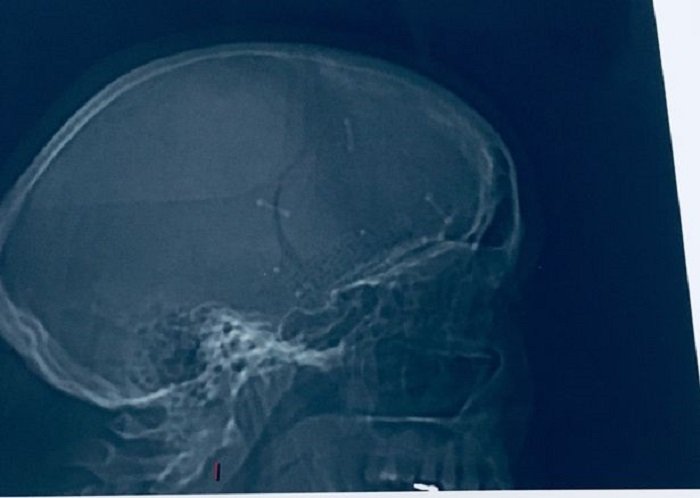

Хирурги додумались отправить женщину на МРТ, которая выявила у нее в мозгу менингиому размером с мяч для гольфа, которая создавала чудовищное давление на глазное яблоко.

Операция длилась 8 часов, в результате которой женщине удалили раковую опухоль и поставили металлическую пластину, закрепив ее на черепе 20 скрепками. Однако врачи предупредили ее, что опухоль может вырасти снова.